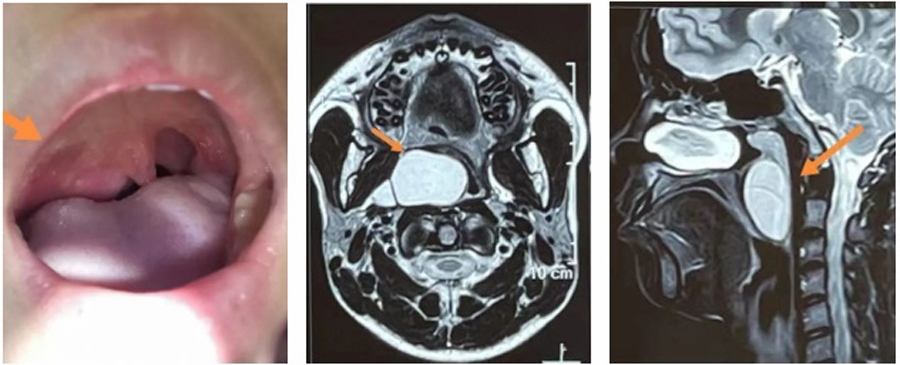

小君因为咽部异物感,右侧面部膨隆来德州扑克游戏网 就诊,平日并没有咽痛、吞咽困难、消瘦等。在检查中,医生发现,小君右侧软腭明显凸出,边缘可见肿物向内下方膨隆、悬雍垂(小舌头)整体左移、腭弓向内下方偏移,鼻咽镜检查发现肿物上极已达鼻咽部后鼻孔层面,下极到喉部会厌缘平面,跨度大,基地宽。根据小君临床表现,估计肿物生长已数年之久,为明确肿物性质,医生立即进行了进一步检查。通过增强CT、核磁检查明确了肿物的边界,上边界达鼻咽顶、下边界在声门上,外边界与颈外侧动静脉相毗邻、内边界将咽部内侧壁完全向内下方挤压。影像显示肿物边界清晰,结合其临床表现,考虑恶性可能性不大,但由于肿物巨大,向内侧已到中线位置,向外侧,小君的右侧面部已出现略向外膨隆状态,手术迫在眉睫。

确定手术治疗后,张薇副院长和团队根据检查情况,积极制定手术方案。手术最大的风险在于肿物的位置特殊,与颈内动静脉关系紧密,稍有不慎损伤,后果不堪设想。手术入路是经内镜从口咽进入?还是经颈外侧切口进入?张薇副院长仔细分析了手术方案:如果从咽部进入,可以避免皮肤切口造成的颈部瘢痕,但对术者的手术能力要求很高,需要内镜辅助,尽量清除囊壁的同时要注意保护好血管;如果从颈外侧进入,切口较大,造成颈部瘢痕,可能影响患儿颈部美观,甚至影响升学,且手术需跨越整个动静脉区,才能到达肿物的位置,并且有形成咽瘘、神经血管损伤等并发症。为避免颈部巨大瘢痕对患儿的影响,儿医团队还是决定经口咽入路,迎接挑战,尽最大努力,保患儿安康。

肿物外壁彻底打开,吸引出大量棕黄色黏稠物,内镜探入腔内观察,可见数个分隔,非常深,直逼颈外侧,其中一个囊腔外侧壁与颈内动静脉完全呈现“共壁”状态,通过内镜,菲薄的囊壁下清晰可见粗大的颈内静脉血管及不断搏动的颈内动脉。这一情况,着实让团队成员心头一紧。安全起见,张薇副院长果断决定保留“共壁”部分的囊壁,剥离、切除囊肿底壁的其他部分。